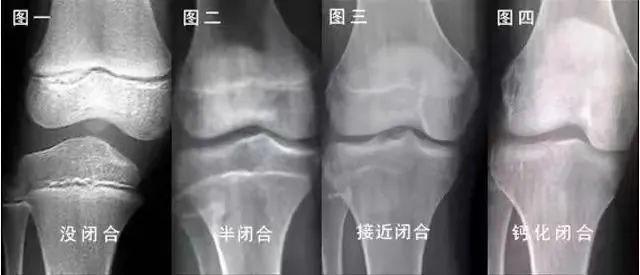

而性发育进展过快,会出现骨龄超前,骨骺提前闭合,影响终身高。

身高的增长伴随着骨骼的发育,主要反映在骨龄。骨龄离骨骺闭合年龄越远,生长的时间越长。

所以个体的差异比较大,如果孩子已经来初潮,想了解孩子生长潜力,可以先了解一下骨龄状况。